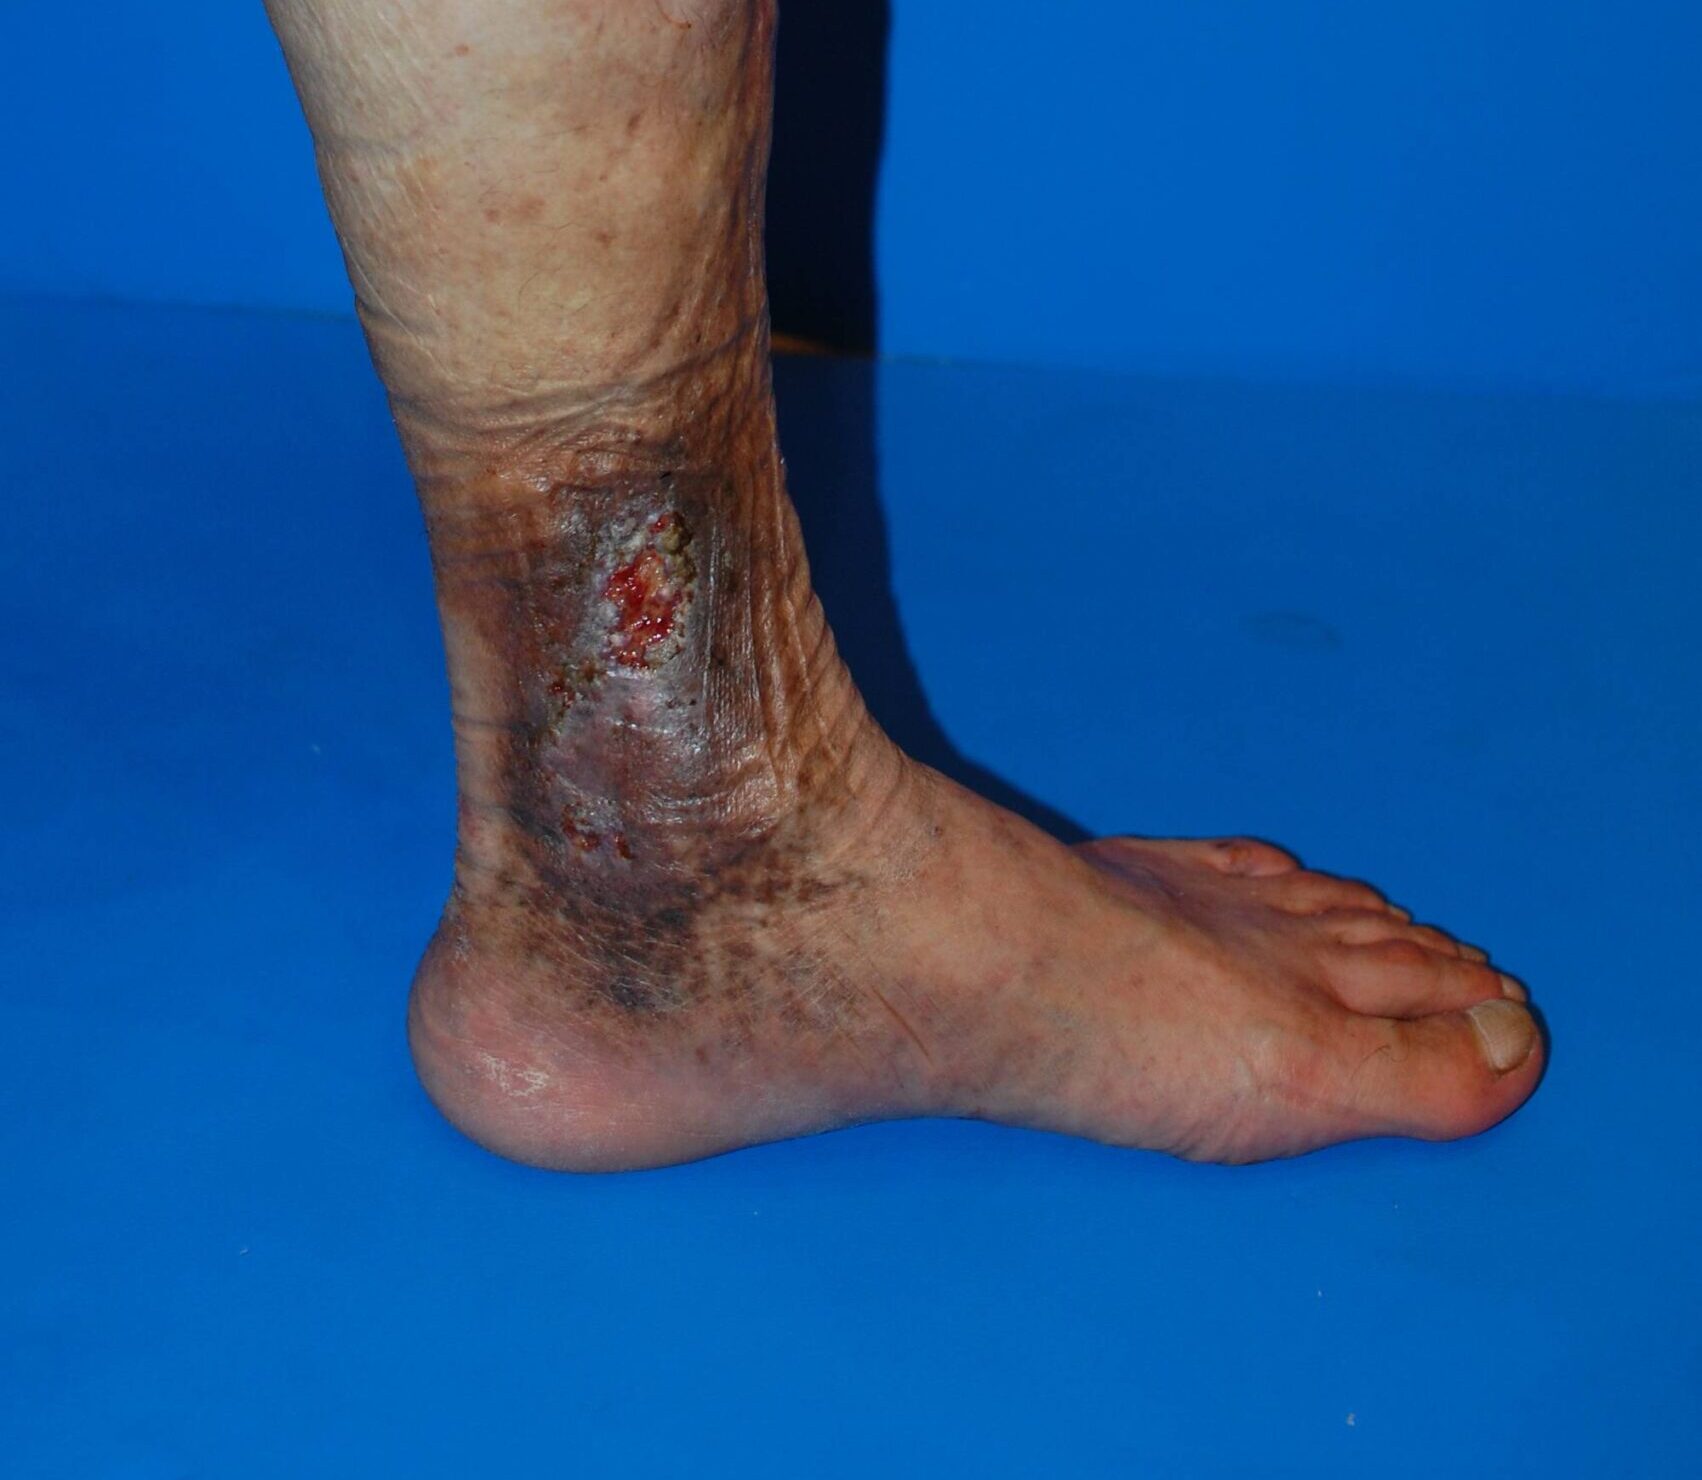

皮膚潰瘍

下肢静脈瘤 皮膚潰瘍